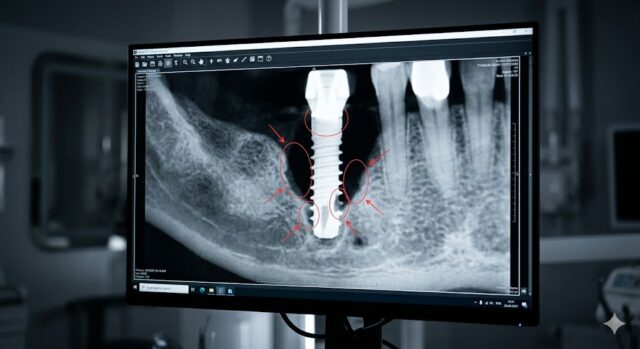

インプラントは、顎の骨に埋め込まれる人工歯根である「インプラント体(フィクスチャー)」、その上に装着される連結部品「アバットメント」、そして最終的に見える部分である「上部構造(人工歯)」の3つの主要なパーツから構成されています。これらを繋いでいるのが精密な「スクリュー(ネジ)」です。

これらのネジが緩むことで、パーツ間にミクロン単位の「隙間」が生じます。そこに細菌が入り込んだり、物理的な振動が加わり続けたりすることで、人工歯がグラついたり、最悪の場合はパーツが折損・脱落したりする原因となります。 ※参照:インプラントパーツの種類と構造について ※参照:ネジ式 vs セメント式を徹底比較!後悔しない固定方式の選び方

- インプラント周囲炎による骨吸収: 毎日のブラッシング不足などで細菌感染が起こり、インプラント周囲炎が進行すると、インプラントを支える骨が溶けて失われます。土台となる骨の支えが少なくなることで、インプラント全体が微妙に揺さぶられるようになり、ネジに本来かからないはずの斜め方向からの負担が増大して緩みにつながります。

- 最新技術による精密診断: 港区・高輪ゲートウェイ駅近くの当院では、デジタルスキャナーや歯科用CTなどの先進設備を導入しています。これにより、肉眼や従来のレントゲンでは見えない微細なズレや骨の状態を立体的に把握し、未然にトラブルを防いでいます。